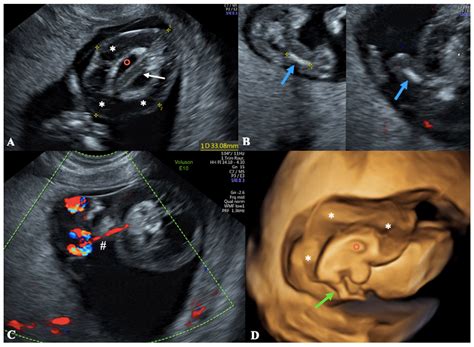

• Nuchal Translucency Measurement: One of the key measurements taken during this scan is the nuchal translucency, which is the fluid-filled space at the back of the baby's neck. This measurement, along with other factors, helps in assessing the risk of chromosomal abnormalities like Down syndrome.